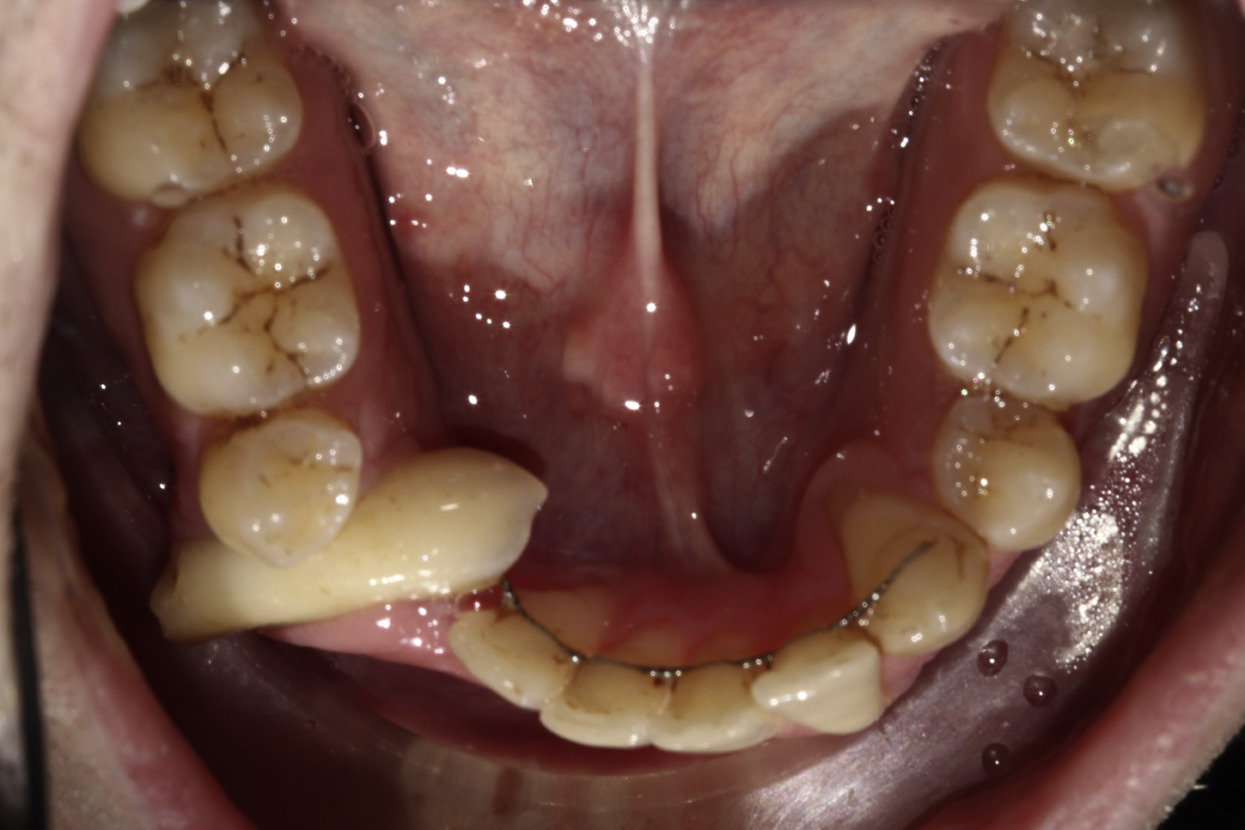

Diş əti (gingiva)

12

1